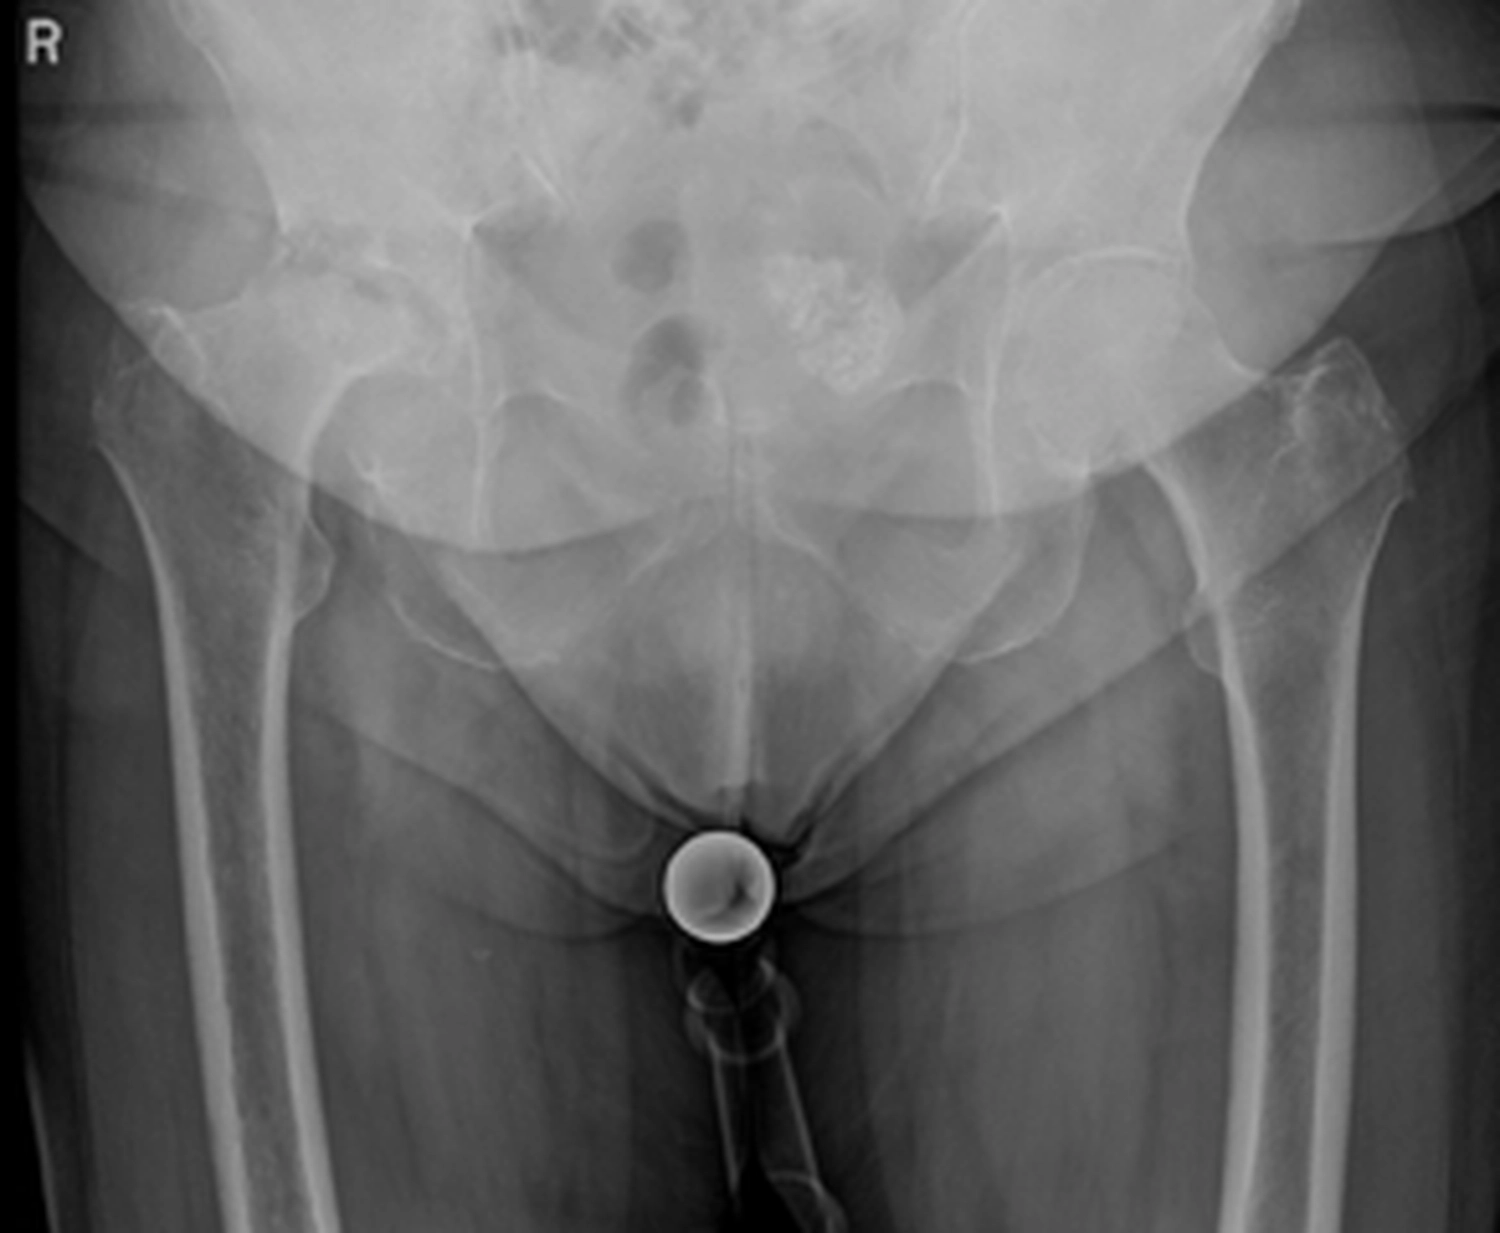

Das Hüftgelenk ist eines der größten und am stärksten belasteten Gelenke des menschlichen Körpers. Mit zunehmendem Alter oder durch Erkrankungen kann es zu einem Verschleiß (Arthrose) oder zu Schädigungen des Gelenkes kommen, die starke Schmerzen und Bewegungseinschränkungen verursachen. Sofern konservative Behandlungen wie Schmerzmedikamente, Krankengymnastik oder Injektionen nicht mehr ausreichen, kann der Ersatz des Hüftgelenkes durch eine Endoprothese notwendig werden.

In Deutschland werden jährlich ca. 230.000 künstliche Hüftgelenke implantiert

Ein künstliches Hüftgelenk wird in der Regel eingesetzt bei: